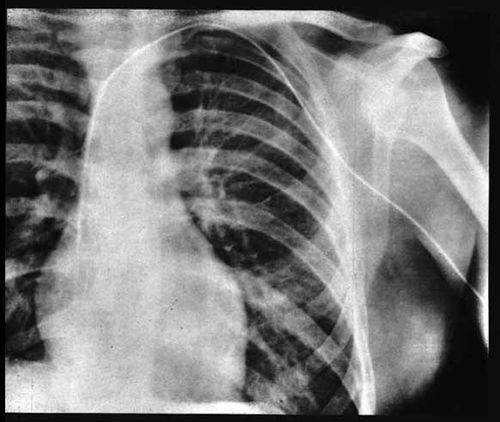

पहिल्या एक्स-रे मध्ये दिसलं की कॅथेटर योग्य जागी पोहोचला नव्हता. मग परत एकदा निकराचा प्रयत्न करून त्याने हा कॅथेटर अक्षरशः पुढे ढकलला आणि परत एकदा एक्स-रे घेतला. यावेळी मात्र कॅथेटर हृदयाच्या उजव्या बाजूकडील वरच्या कप्प्यात म्हणजेच राइट ऑरिकलमध्ये पोहोचल्याचं दिसलं. मोठा विलक्षण क्षण होता तो! आजवरच्या कल्पनेचं हे सत्य स्वरूप होतं, शिवाय इतरांना दाखवण्यासाठी एक्स-रे च्या स्वरूपात भक्कम पुरावा प्राप्त झाला होता.